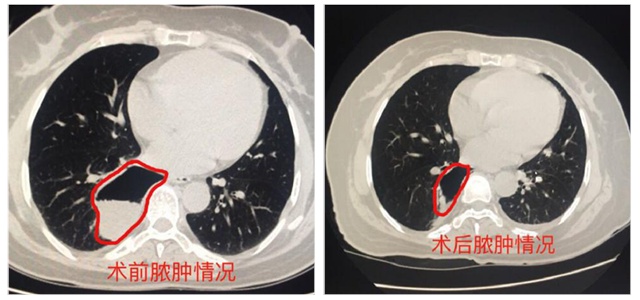

術(shù)后患者咳嗽明顯減輕,復(fù)查CT提示膿腫縮小,膿腔內(nèi)積液減少,經(jīng)呼吸內(nèi)科醫(yī)護人員后續(xù)治療及護理后,患者病情逐日好轉(zhuǎn),術(shù)后一周多出院。

術(shù)前術(shù)后情況對比